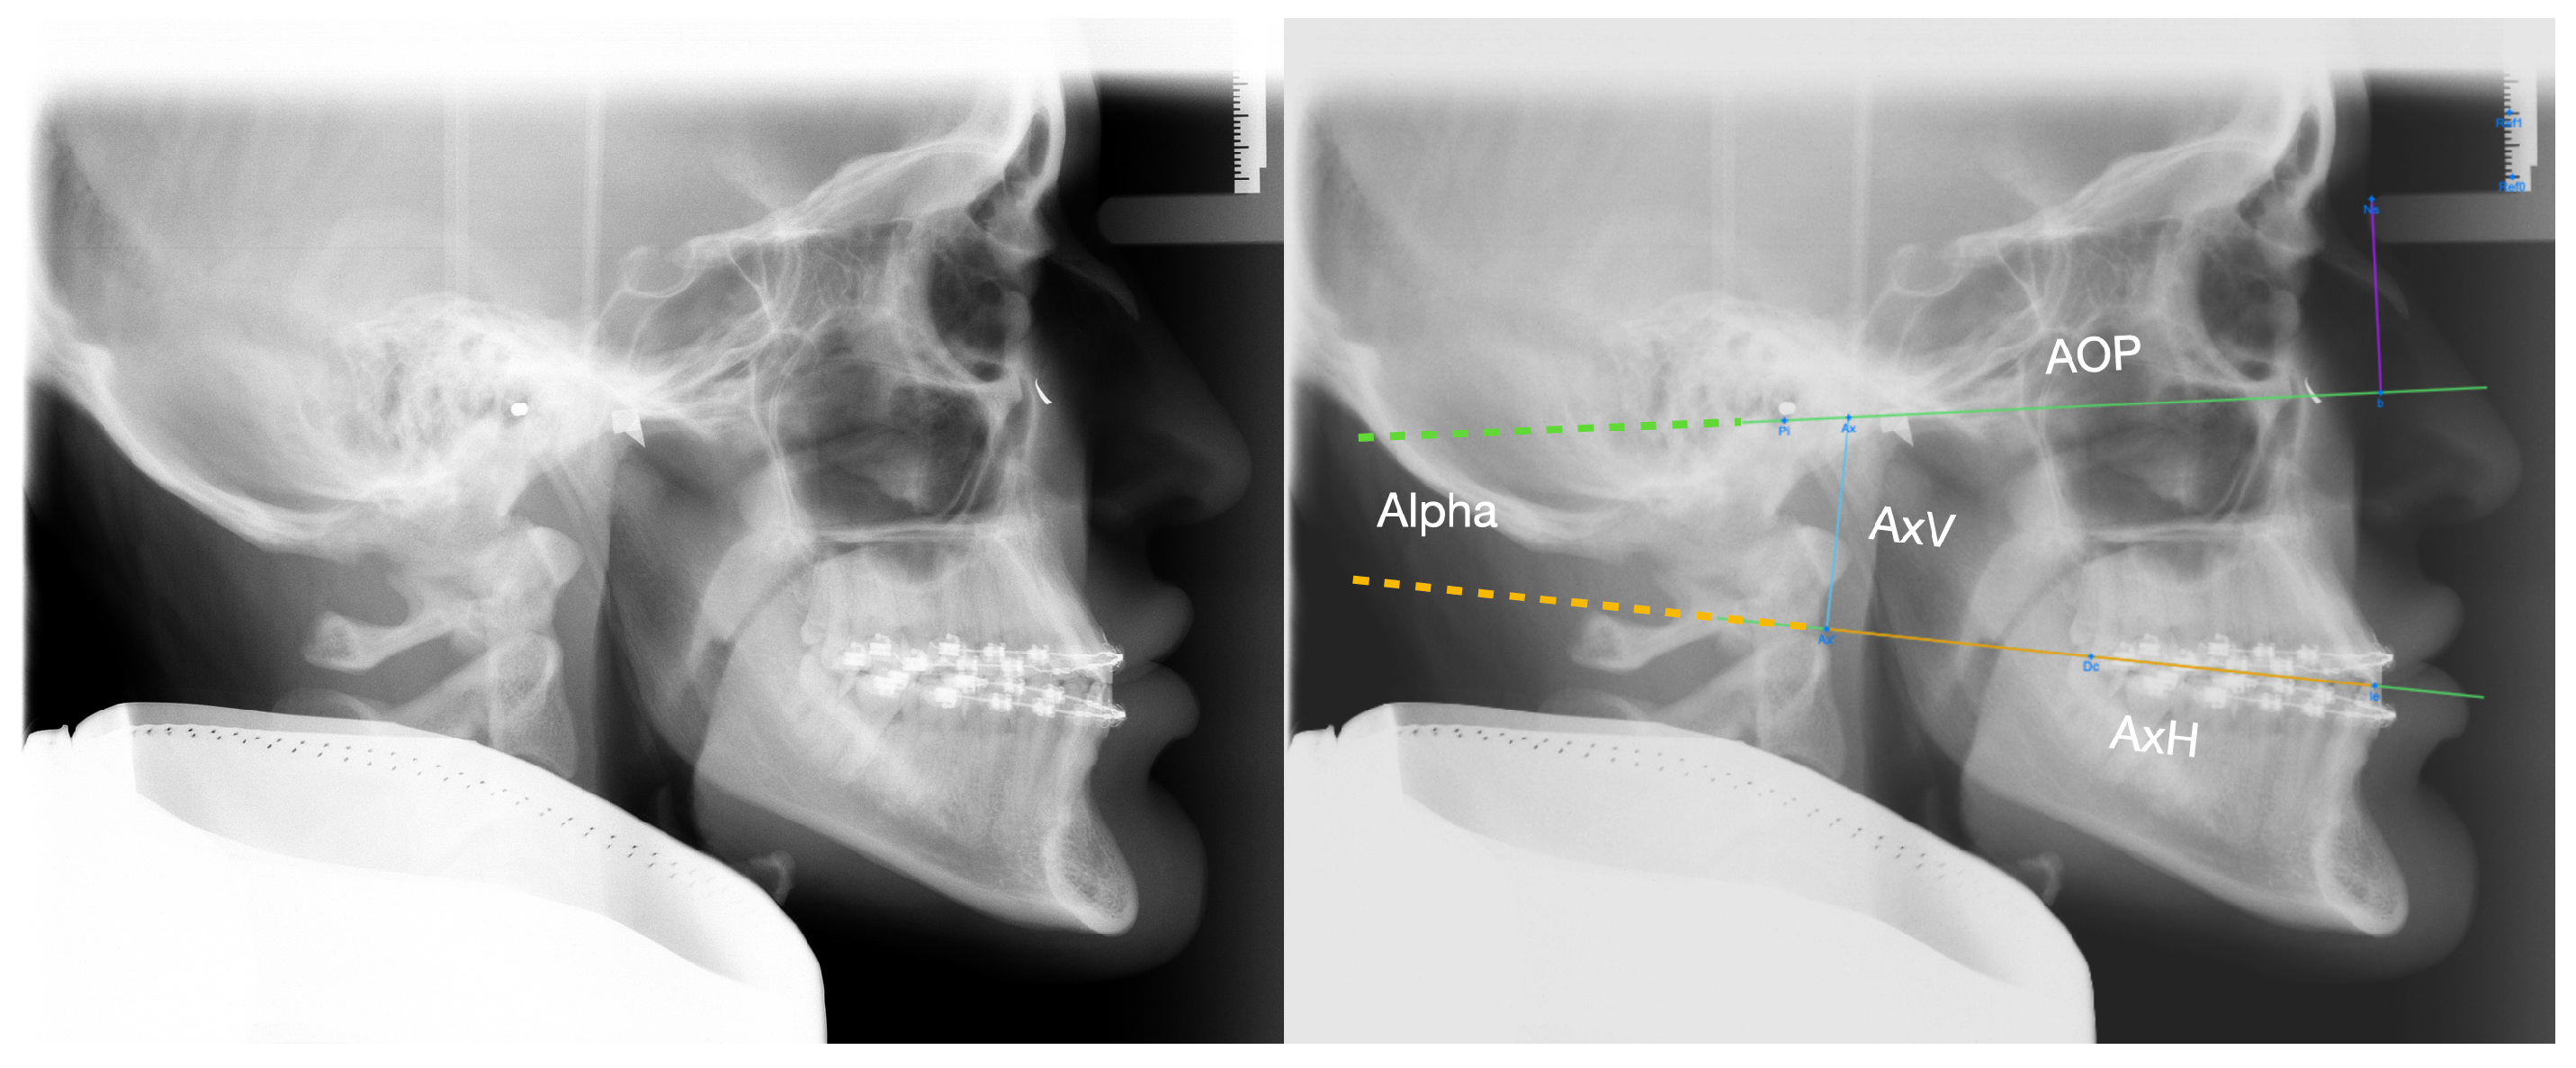

| AxV | 323 | 30.2 | 5.7 | 191 | 35.8 | 5.7 | <0.001 |

| AxH | 323 | 88.0 | 6.7 | 191 | 93.1 | 8.1 | <0.001 |

| AxV | 128 | 36.2 | 4.6 | 204 | 26.5 | 3.8 | 182 | 35.9 | 4.5 | <0.001 1 | |

| AxH | 128 | 98.9 | 5.5 | 204 | 88.1 | 5.4 | 182 | 85.6 | 5.6 | <0.001 | |